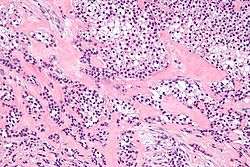

Micrograph of a hyalinizing clear cell carcinoma showing the characteristic clear cells and surrounding hyalinized stroma. H&E stain.

HCCC consist of cells with abundant clear cytoplasm, arranged in cords, trabeculae or clusters in a hyalinized stroma.[4] Nuclear pleomorphism is usually minimal and mitoses are infrequently seen.[2]

Owing to their glycogen content, which explains the "clear" appearance under the microscope, tumour cells stain with PAS. Immunostains for S100 and smooth muscle actin (SMA) are typically negative, but positive for cytokeratins and epithelial membrane antigen (EMA).